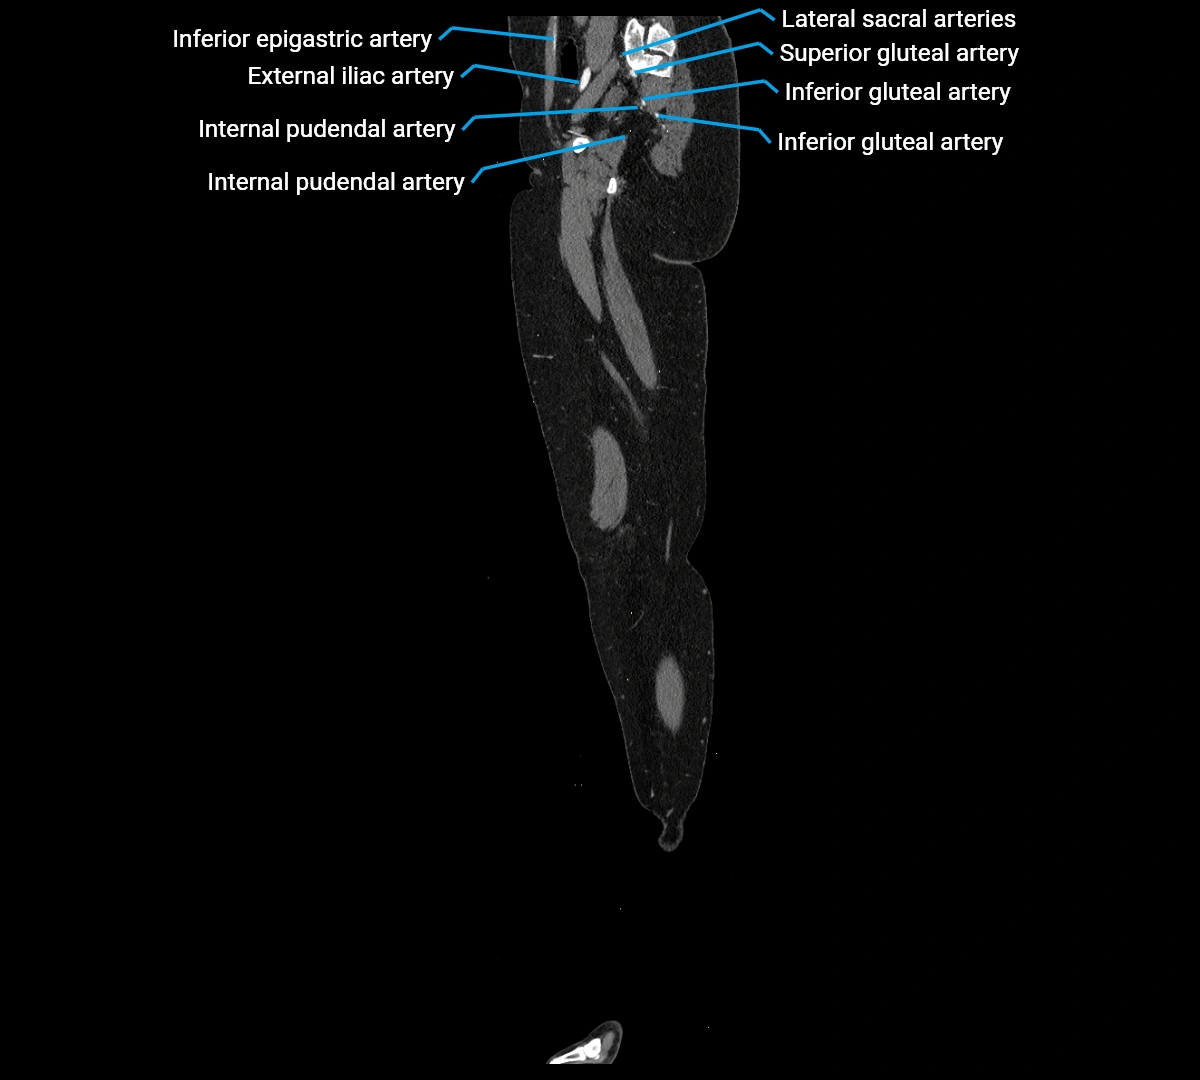

CT images

image

Contrast-enhanced CT (CTA):

• Gold standard for abdominal aortic imaging

• Provides excellent detail of lumen, wall, aneurysm, thrombus, and branch vessels

• Multiplanar and 3D reconstructions help in aneurysm measurement, stent graft planning, and dissection evaluation